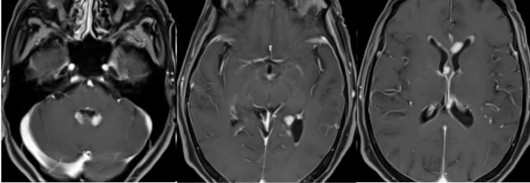

(二)少见鉴别诊断病例

68岁女性,因记忆力减退、认知障碍伴精神症状就诊,表现为分不清上下午、自言自语与已故亲人说话。病变位于第四脑室旁、侧脑室三角区周围及胼胝体。与MS相比,年龄、症状不同,脑室旁及胼胝体受累表现不符合MS。起初一线检查报为老年性脱髓鞘改变,后经增强检查,所有病灶明显且均匀强化,室管膜也有异常强化,最终确诊为中枢神经系统淋巴瘤,PET检查也证实了该诊断。